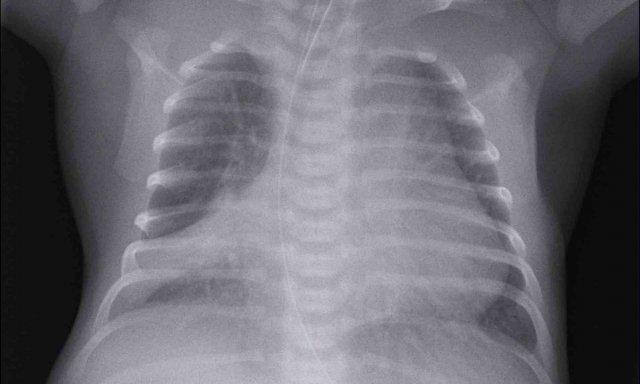

Hình ảnh

Trẻ sơ sinh một ngày tuổi, tuổi thai 27 tuần.

Mờ dạng hạt cả hai phổi.

Mạch máu và bóng tim được hiển thị rõ ràng.

Conclusion: RDS grade 1.

Đường truyền catheter trung tâm qua đường ngoại vi (PICC) bị cuộn trong tâm nhĩ phải. Đường PICC cần được rút lui đến mức tĩnh mạch chủ trên và tâm nhĩ phải.